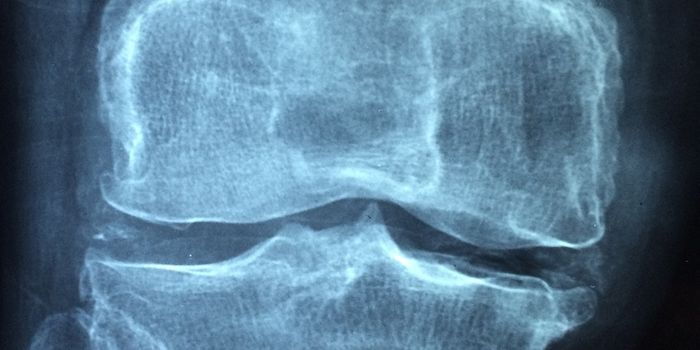

APR 30, 2024Clinical & Molecular DXIn osteoarthritis, the tissues that cushion joints begin to degenerate, leading to stiffness, pain, and swelling. Accord ...